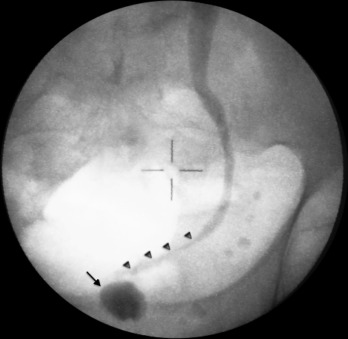

Foi realizada injeção de contraste pela nefrostomia (fig. 1 ) que mostrou estenose grave do ureter terminal (setas pequenas), bem como bexiga de muito baixa capacidade (seta).

Pré‐operatório: bexiga de baixa capacidade (seta) e estenose do ureter terminal (setas pequenas) após injeção de contraste pelo cateter de nefrostomia.